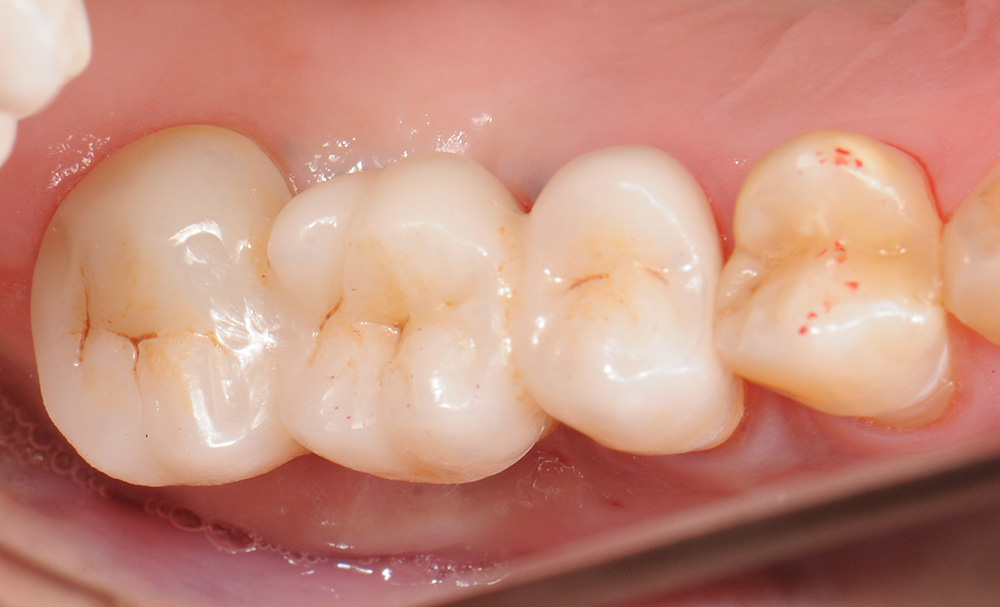

case8 症例(セラミックインレー・ダイレクトボンディング)

治療前

治療後

| 費用(税込み) | セラミックインレー:66,000円、ダイレクトボンディング:22,000円 |

|---|---|

| 治療回数 | 1歯につき3回 |

| 主訴 | 金属の修復物を白くししたい |